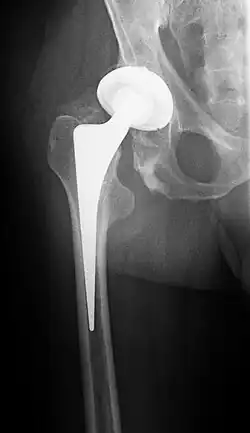

Endoprothese

Der endoprothetische Ersatz des Hüftgelenks ist die mit Abstand häufigste operative Therapiemaßnahme. Dabei werden normalerweise sowohl der Femurkopf als auch die Hüftpfanne ersetzt, man spricht daher von einer Totalendoprothese (TEP). Die Prothese kann dabei im Knochen durch Knochenzement verankert oder durch eine spezielle poröse Oberfläche ohne Zement fixiert sein. Die – ebenfalls gebräuchliche – Kombination aus zementiertem Schaft und zementfrei implantierter Pfanne wird als Hybridsystem bezeichnet. Für die Gleitpaarung können verschiedene Materialien (in der Regel: Keramik-Kopf und hochvernetzte Polyethylen-Pfanne) verwendet werden.[29]

Mittlerweile wird vermehrt auf minimalinvasive, d. h. muskel- und knochenschonende, Operationszugänge gesetzt, welche zudem ein ästhetisches Operationsergebnis versprechen.[31] Aus diesem Grund sind in den letzten Jahren auch kurze bzw. kürzere Schaftprothesen (Kurzschaftprothesen) entwickelt worden (Jerosch 2017).

Bei einem komplikationslosen Verlauf dauert eine solche Operation rund eine Stunde.

Besonders die endoprothetische Versorgung hat eine sehr gute Langzeitprognose, circa 95 Prozent der implantierten Endoprothesen sind auch nach 10 Jahren noch funktionstüchtig. Gemäß dem Swedish Hip Arthroplasty Register mussten selbst nach 26 Jahren 75 Prozent der Hüftendoprothesen nicht ausgetauscht werden. Derselben Studie zufolge ist auch eine erneute Wechseloperation (Re-Revision) kaum wahrscheinlicher als eine Revision, denn nach zehn Jahren sind – statistisch – immer noch mehr als 80 Prozent der Zweitprothesen in situ.[35]